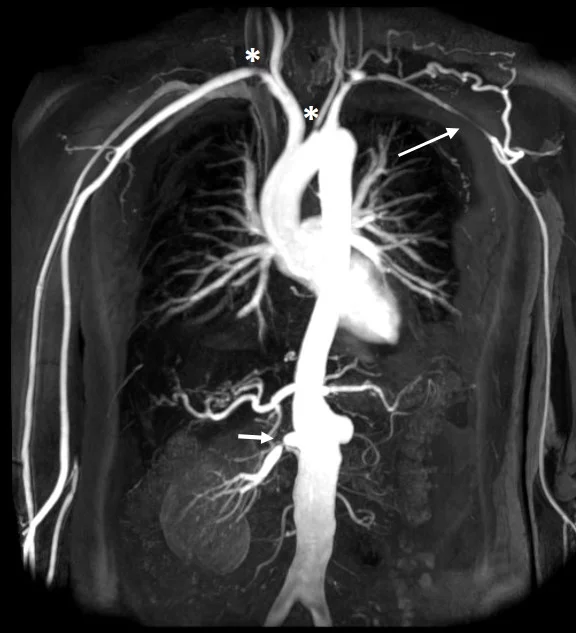

آنوریسم های عروقی

آنوریسم نوعی بیماری عروقی است که دیواره رگ به طور غیر طبیعی گشاد می شود و امکان پارگی عروق حیاتی مانند شریان آئورت در این موارد بسیار بالاست

آنژیوگرافی چیست؟ در پاسخ به این سوال باید بگوییم آنژیوگرافی پروسجری است که توسط پزشکان برای دیدن عروق خونی درون بدن انجام می گیرد. در بدن انسان عروق خونی به دو دسته اصلی تقسیم می شوند: شریان ها و ورید ها. عروق خونی وظیفه انتقال خون در سراسر بدن را به عهده دارند. اگر پزشک به وسیله آنژیوگرافی ورید ها را تحت ارزیابی قرار دهد به آن ونوگرافی می گویند. و اگر عروق شریانی تحت آنژیوگرافی قرار بگیرد به آن آرتریوگرافی گفته می شود.